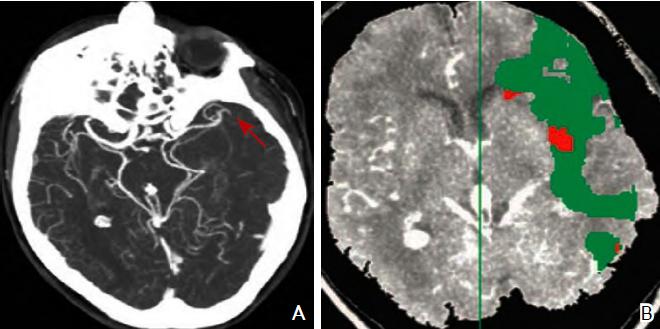

CT灌注成像对于梗死核心灶标记为CBV降低的区域,CBF与MT T以低于界定的阈值(CBV<2 ml/100 g、CBF<20 ml/100 g/min及MTT>8 s)来显示脑的异常灌注区。缺血半暗带为脑梗死核心区与异常灌注区域之间的差异区域(图3)。

图3 CT血管造影(A)及CT灌注成像(B)注:A:CT血管造影显示大脑中动脉闭塞(红色箭头所示);B:CT灌注成像,绿色区域为平均通过时间(MTT)异常区域(MTT 145%,与对侧正常比较),红色区域为脑血容量(CBV)降低区域(CBV<2.0 ml/100 g)。CT:计算机断层扫描

MRI PWI常采用动态磁敏感对比增强技术,通过对比剂团注追踪技术进行动态增强扫描,依靠对比剂磁化率改变引起信号变化的原理成像。经处理后可得出相应灌注成像的参数如CBF、CBV、MTT及TTP等。研究表明,CBF下降和MTT延长是组织缺血的相对敏感指标,但存在过分估计最终梗死体积的可能性;TTP图像上脑灰质、白质之间无明显区别,可以清楚显示病变的范围和边界。虽然目前识别缺血半暗带的方法有多种,但MRI DWI与PWI不匹配区是急诊过程中判断缺血半暗带较切合实际的方法(图4)。一项回顾性研究认为,PWI的病灶面积是DWI病灶面积的2.6倍时早期再灌注的治疗效果最好。

图4 磁共振成像DWI-PWI不匹配区影像 注:A:磁共振DWI序列:高信号的梗死区(粉色标记区);B:磁共振PWI序列:梗死区周围的缺血半暗带(绿色标记区)。DWI:弥散加权成像;PWI:灌注加权成像